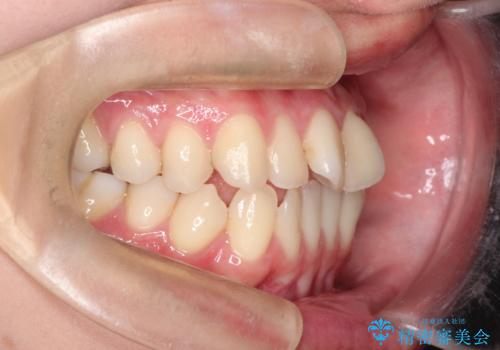

インビザラインによる非抜歯矯正 ガタガタな歯並びを整った歯並びへ

- 前歯のガタガタを主訴に来院されました。

抜歯矯正も考えられる状態でしたが、非抜歯矯正を希望されました。

使用時間を守っていただけたので、スムーズに治療を終わることができました。